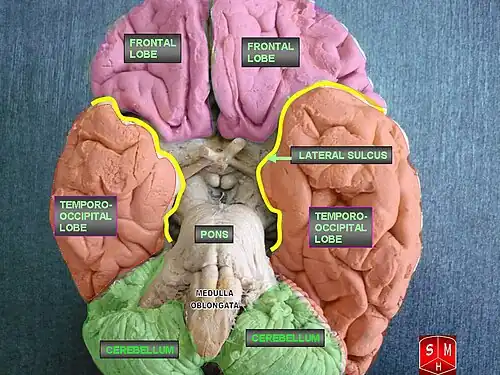

Model images

-

Inferior view of cerebrum.

Inferior view of cerebrum. -

Both hemispheres. Left and right lobes are color-matched.

Both hemispheres. Left and right lobes are color-matched. -